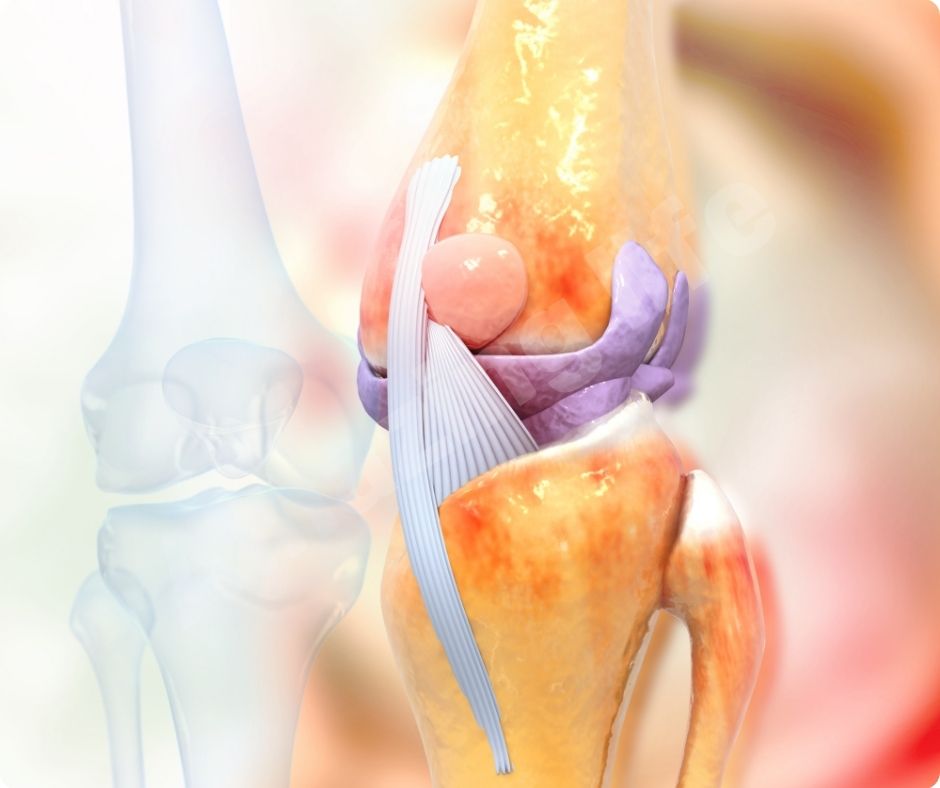

염증 감소

글루코사민의 효능은 염증을 감소시키는 데도 효과적입니다. 관절염은 염증으로 인해 발생하는 경우가 많으므로, 글루코사민을 통해 염증을 줄이면 관절염 증상을 완화할 수 있습니다. 이는 자연적인 방법으로 관절 건강을 유지하는 데 유용합니다.